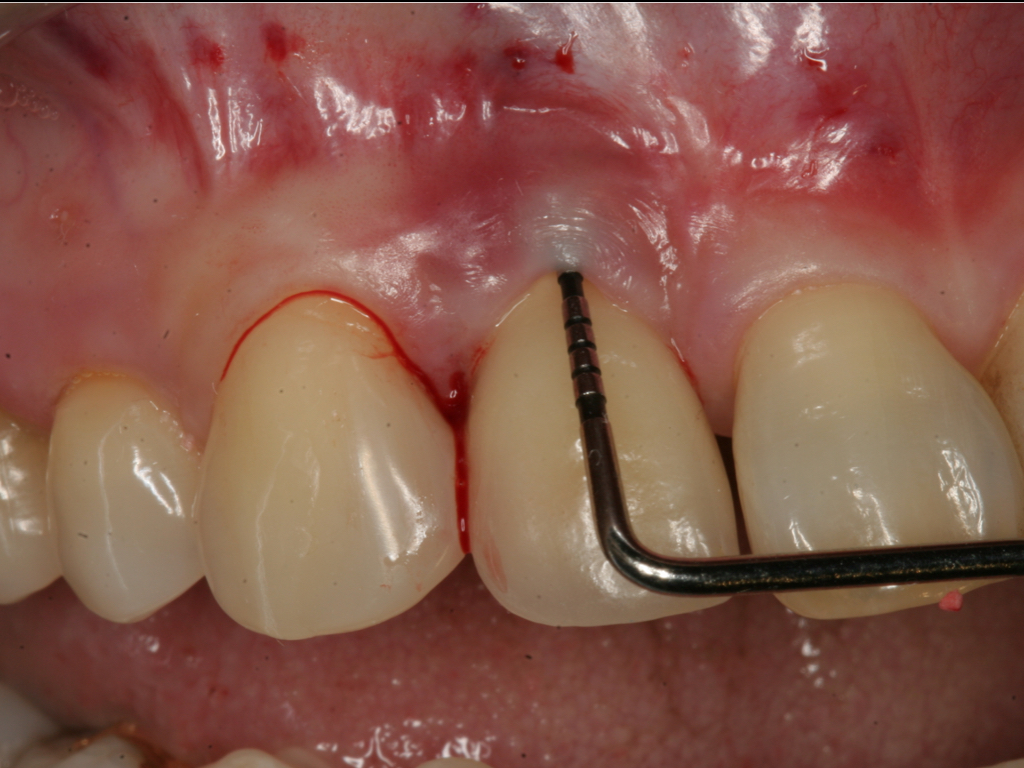

Fig 7. Probing of the buccal surface reveals additional loss of attachment around the dental implant.

Figure 7

Fig 8. Flap elevation confirms circumferential bone loss.

Figure 8

Probing is useful to determine the presence of biological complications at the buccal and lingual sites of implants, which cannot be evaluated on a radiograph (Figure 6 through Figure 8). Because of the absence of a periodontal ligament, bone loss on the buccal and lingual aspects of an implant indicates loss of support for the implant and may be a sign of additional circumferential bone loss around the implant.35